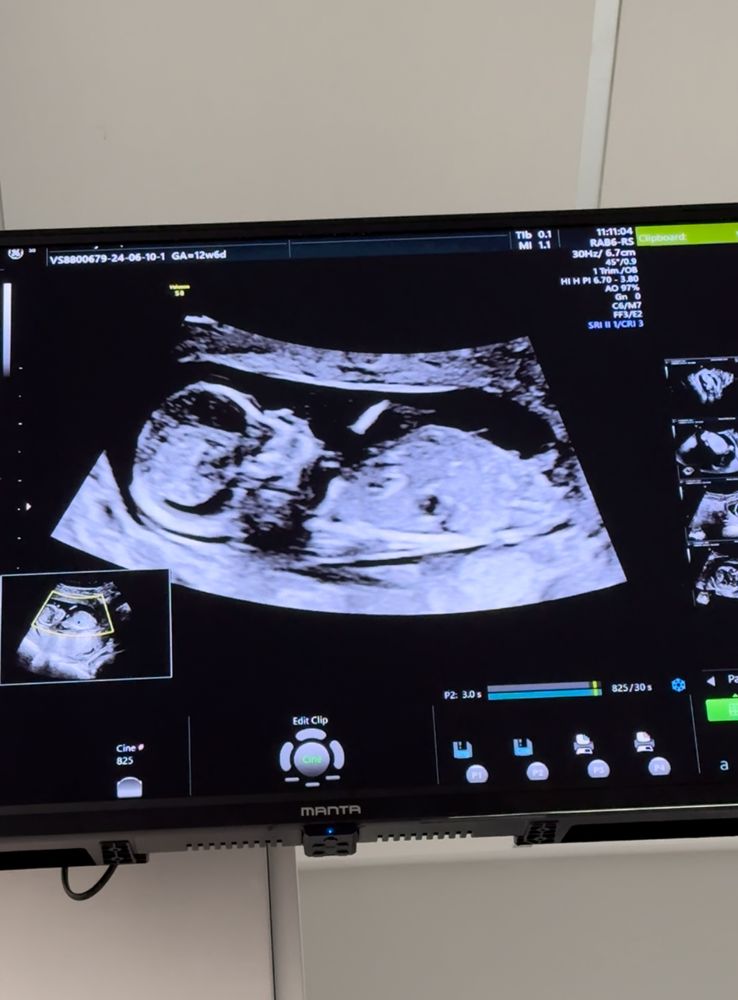

Пол малыша в 12,6 недель 🤔

По бугорку девочка

Ждём дочку!😍🤭 16 недель определение пола